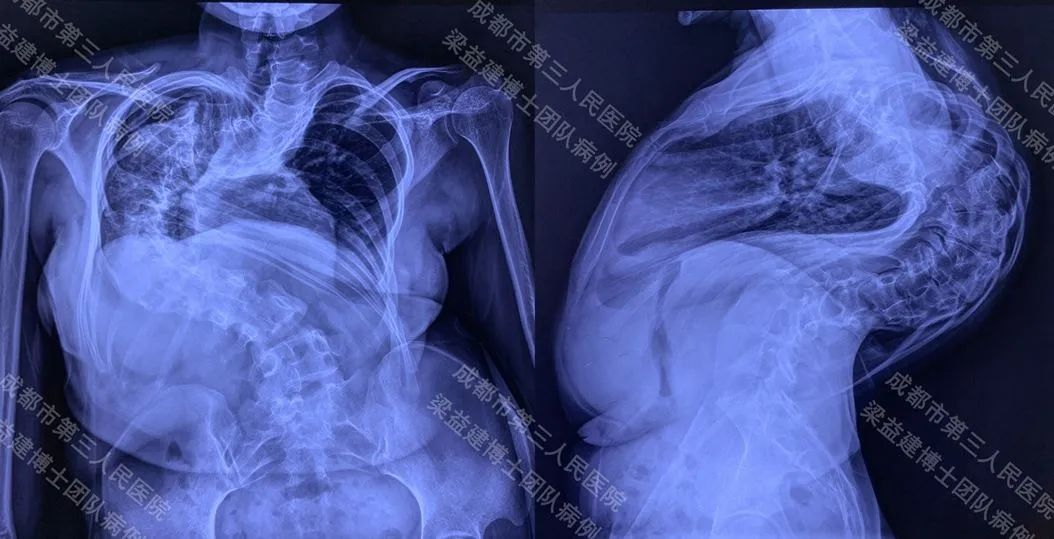

A 27-year-old female patient was admitted to the hospital because of "scoliosis and kyphosis found for 20+ years". After thorough examination, the diagnosis was: 1. Very severe spinal deformity, with 160 degrees of scoliosis and 150 degrees of kyphosis; 2. Thoracic deformity; 3. Very severe impairment of lung function (very severe mixed ventilatory dysfunction).

The preoperative height was 138cm, the weight was 39kg, and the arm length was 160cm.